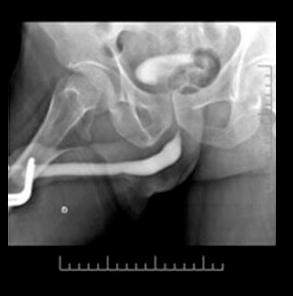

Imagem de Estenose Uretral

Uretrografia mostrando uma estenose severa no segmento da uretra bulbar.